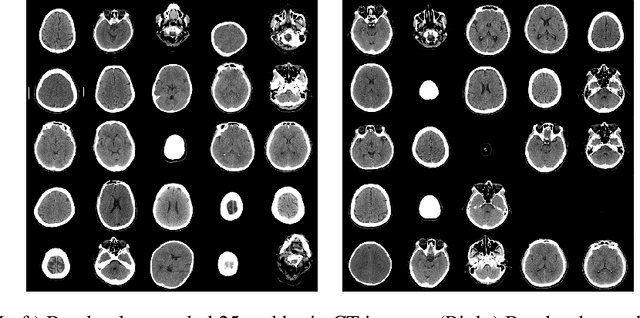

Abstract:Evaluating the performance of generative models in image synthesis is a challenging task. Although the Fr\'echet Inception Distance is a widely accepted evaluation metric, it integrates different aspects (e.g., fidelity and diversity) of synthesized images into a single score and assumes the normality of embedded vectors. Recent methods such as precision-and-recall and its variants such as density-and-coverage have been developed to separate fidelity and diversity based on k-nearest neighborhood methods. In this study, we propose an algorithm named barcode, which is inspired by the topological data analysis and is almost free of assumption and hyperparameter selections. In extensive experiments on real-world datasets as well as theoretical approach on high-dimensional normal samples, it was found that the 'usual' normality assumption of embedded vectors has several drawbacks. The experimental results demonstrate that barcode outperforms other methods in evaluating fidelity and diversity of GAN outputs. Official codes can be found in https://github.com/minjeekim00/Barcode.